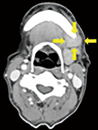

図❸ 初診時のCT画像

画像所見:パノラマX線写真では左側臼歯部にインプラントが埋入されていたが、周囲の骨の吸収像や骨の硬化像は認めなかった(図❷)。造影CTでは左側下顎体部尾側から骨内側に軟部腫瘤があり、腫瘤は造影効果を認めた(図❸)。内部は均一で、境界は比較的明瞭であった。また、膿瘍を疑う液貯留は認めなかった。PET検査では、腫瘤に一致してSUVmax=17.6のFDGの集積を認めた。